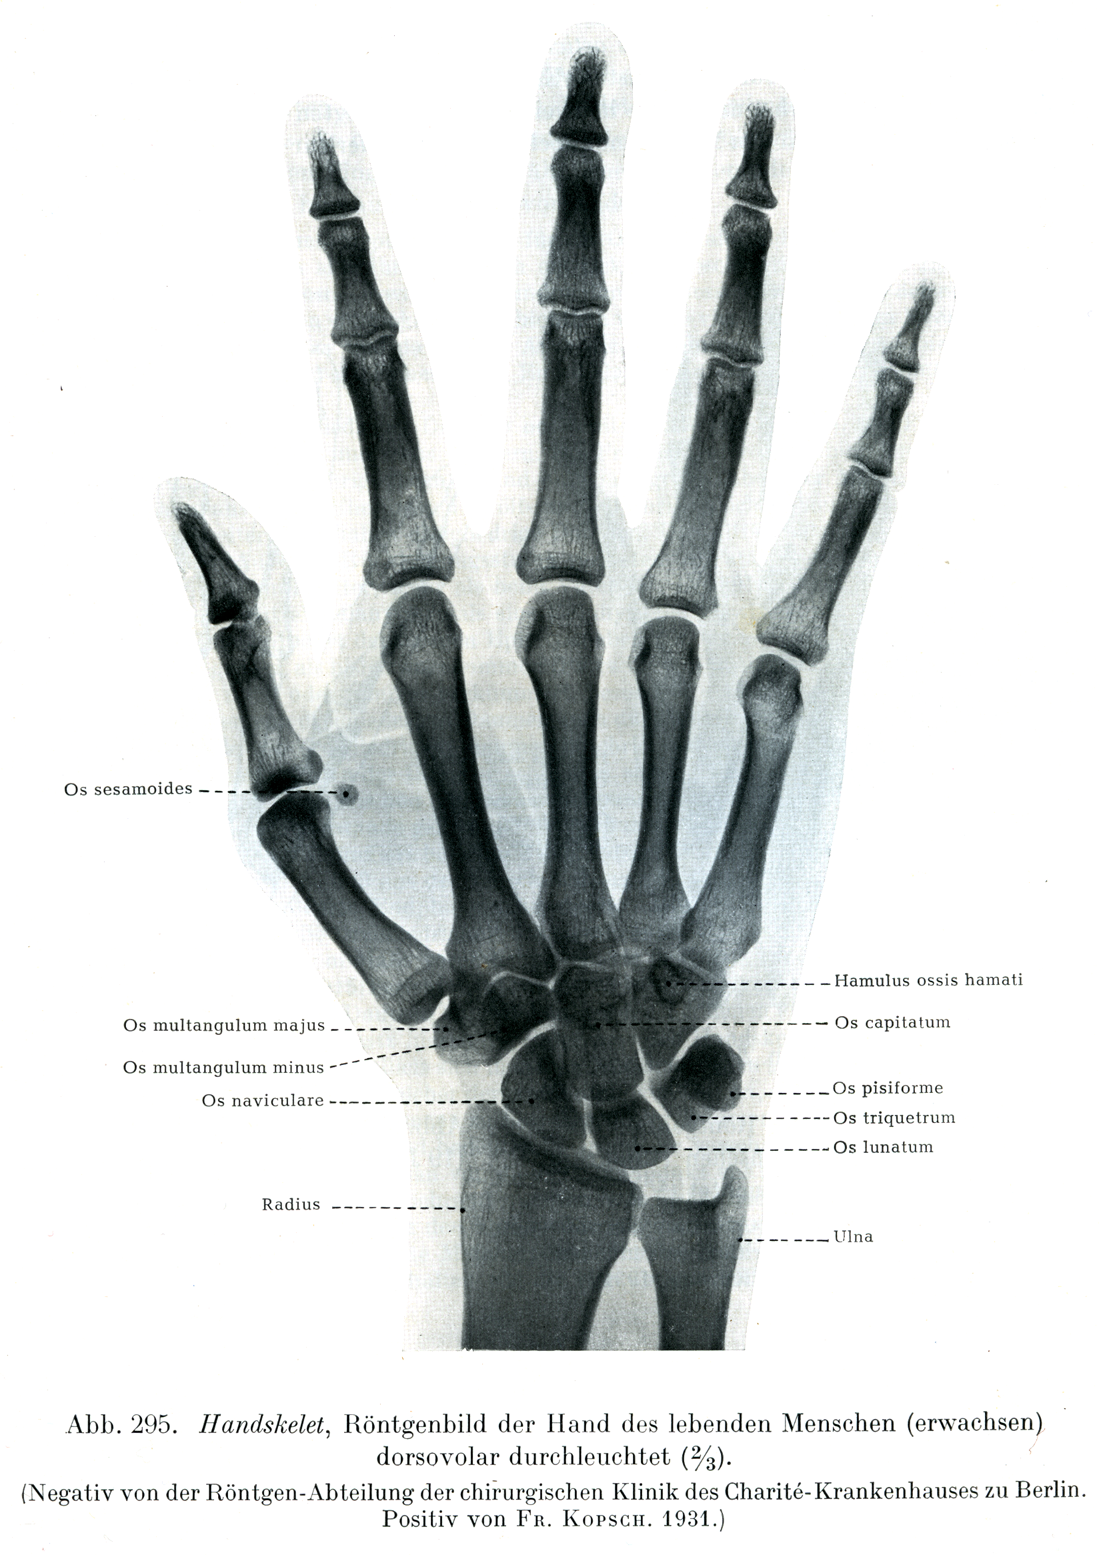

Rauber Kopsch Band1. Abb-295

[図295]

手の骨格

生体(成人)の手のX線像.背掌照射(2/3)